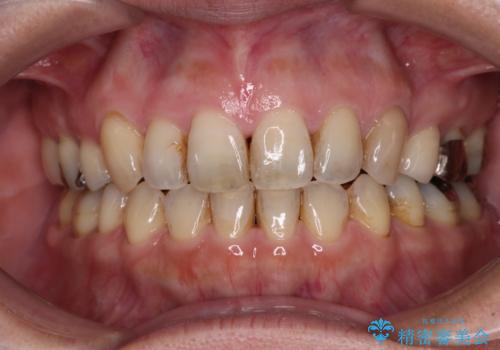

- 八重歯と前歯の隙間を気にして来院された患者様です。

下顎前歯は2本欠損しており、それが原因で隙間ができていました。

また、その影響で上下歯列がアンバランスとなっており、上下前が非接触となっていました。

上下のバランスを取って八重歯などを解消するため、上顎左右第1小臼歯を抜歯することとしました。

根管治療の必要な歯も2本あったため、まずは根管治療を行い、ワイヤー矯正の後に補綴治療を行うこととしました。